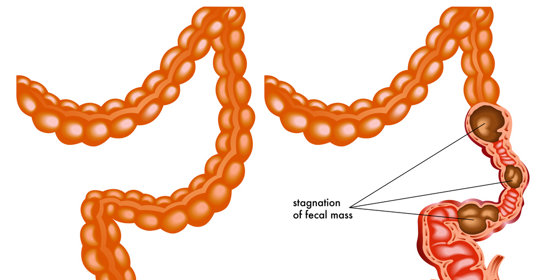

孕婦左側睡大腿褥瘡

褥瘡是由於身體區域性長期受壓,使血液循環受到障礙,皮膚和皮下組織出現持續缺血、營養不良而致的組織潰爛壞死。孕婦左側睡大腿出現褥瘡可能是長期臥床導致的,也有可能與孕期荷爾蒙變化有關。